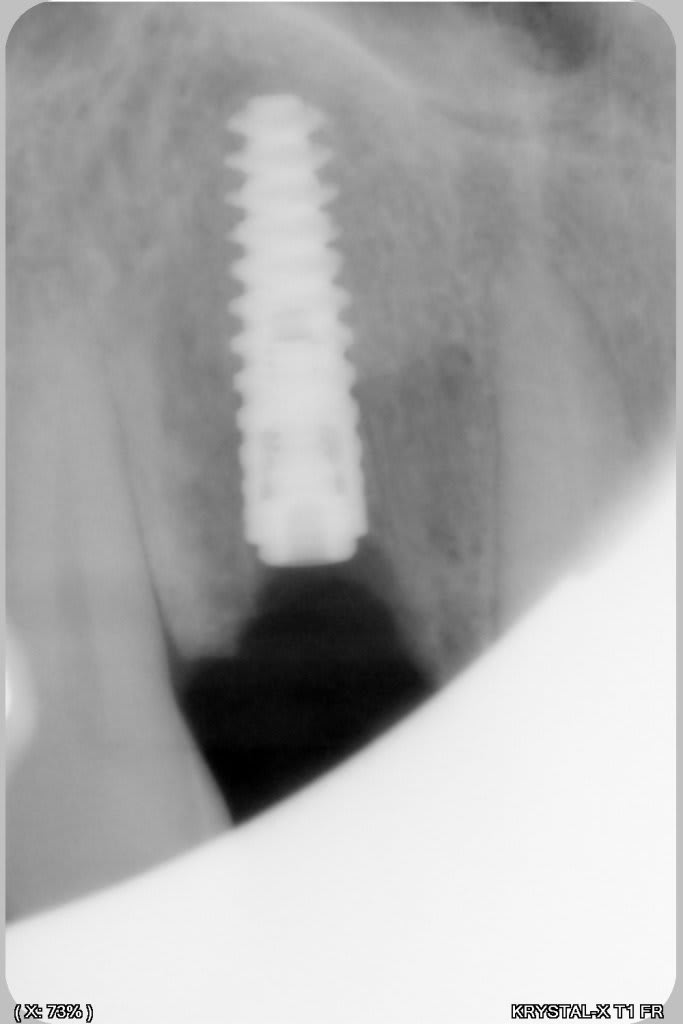

un petit cas comme j'aime, perte de 11, avec atteinte de la paroi vestibulaire.

Manipulation de la paroi palatine, afin de déplacer la moitié de l'os en vestibulaire, et pose d'un Px (Anthogyr) utilisation, de lame 11, ostéotome demi lune de Tatum, spreader (Meissinger) et divers.

Le plus bluffant quand tu fais défiler les photos c’est que tu passes de la dernière (avec l’implant en place) à la 1ere avec la fenestration!

de mémoire un PX 34100 ou 34120

effectivement, mais c'est un des avantage de l'expansion, mais dans ce cas là, il y aura largement les 2mm, l'os déplacé en vestibulaire permet de "fermer la boite " qui avait déjà 3 belles parois.